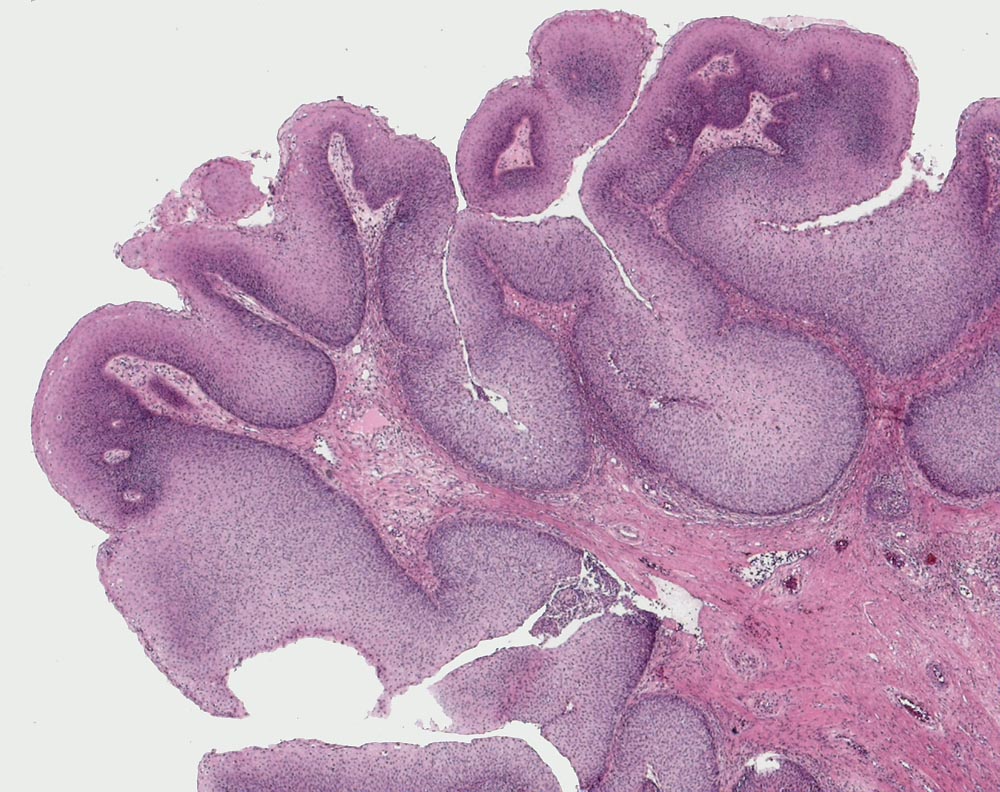

exophytisches Schneider'sches Papillom

Verzweigende exophytische Proliferate mit fibrovaskulären Stromastielen bedeckt von stark verdicktem gut differenziertem nicht verhornendem Plattenepithel.

Exophytische Schneider'sche Papillome können assoziiert sein mit einer HPV-Infektion der low risk HPV-Typen 6 und 11. Hier liegen eindeutige koilozytäre Veränderungen vor, welche auf eine HPV-Infektion hinweisen.